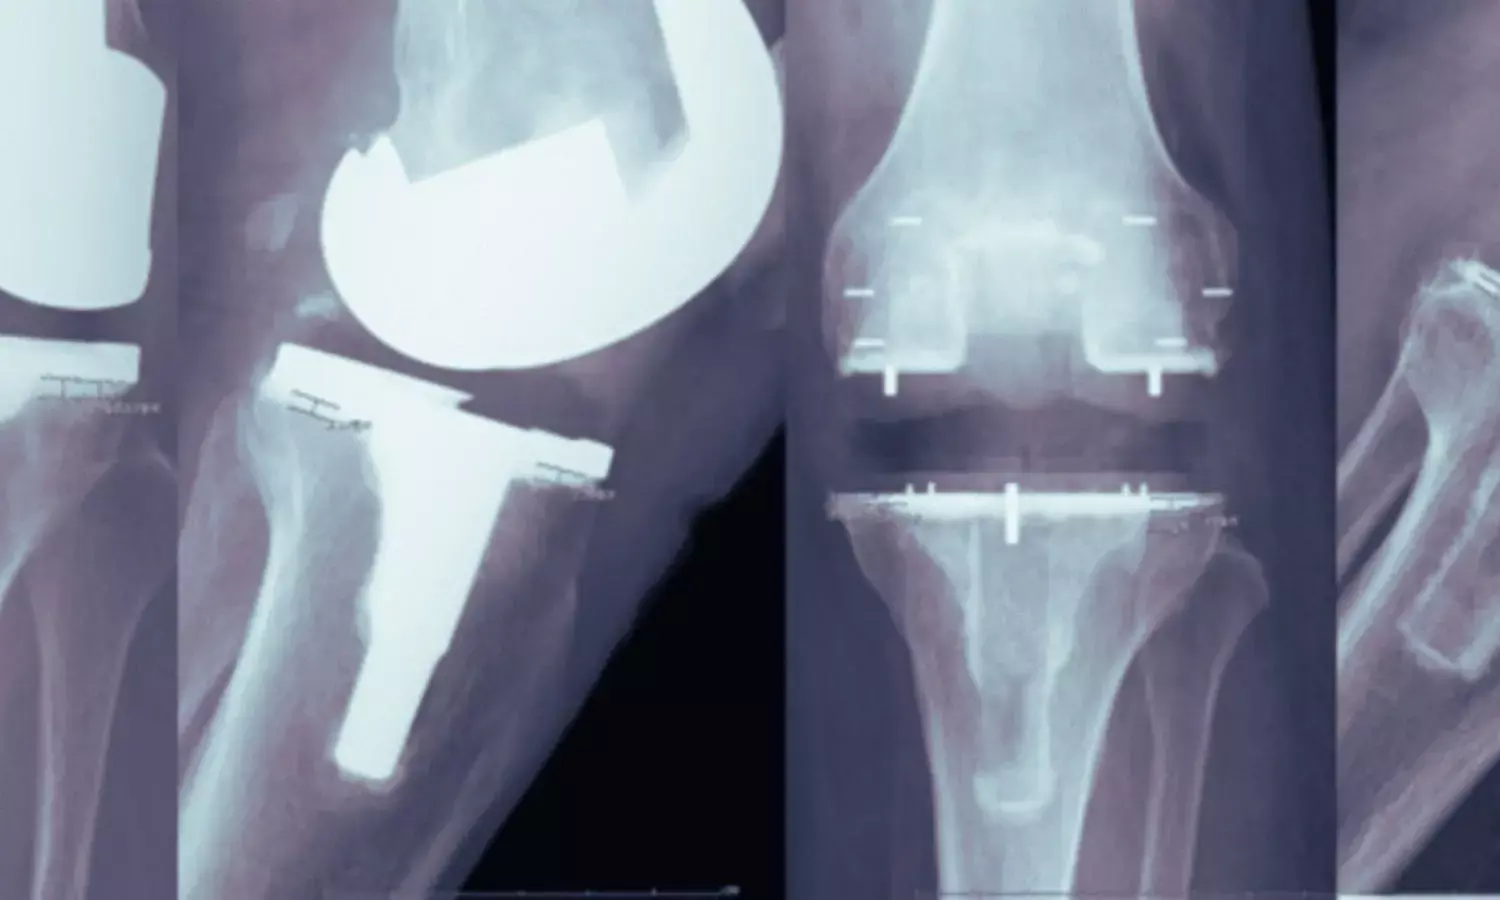

A key clinical advantage of PEEK highlighted in the review is its radiolucency. Unlike metal implants, PEEK does not create imaging artefacts on CT or MRI scans, allowing clearer visualisation of the bone–implant interface, and is light-weight. Coauthor Dr Abhishek Vaish explained, “The radiolucent nature of PEEK enables early detection of complications such as loosening or infection and improves postoperative monitoring.” He added that in procedures such as total knee arthroplasty, PEEK’s flexibility may promote more physiological load transfer and help preserve periprosthetic bone density.